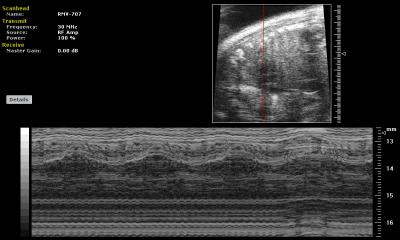

Scientists have long viewed in utero blood stem cell transplantation as a promising treatment strategy for many genetic diseases diagnosed as early as the first trimester of pregnancy, including sickle cell disease and certain immune disorders. Fetal stem cell transplantation involves taking healthy cells from the bone marrow of a donor and transplanting them into the fetus through ultrasound-guided injections. When successful, the implanted cells, or graft, replenish the patient's supply of healthy blood-forming cells.